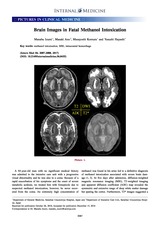

Yoshiro Hadano Junichi Honda

vol.56, no.15, pp.2085-2085, 2017-08-01 (Released:2017-08-01)

参考文献数

2

被引用文献数